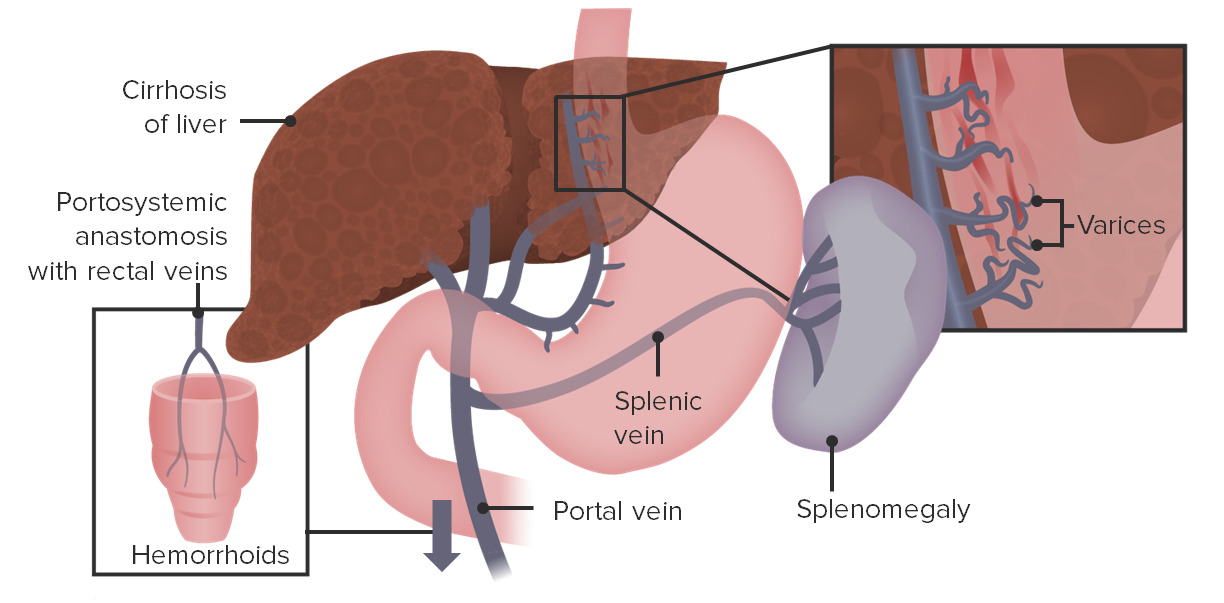

Why Does Portal Hypertension Cause Esophageal Varices Student Doctor

Portal Hypertension USMLE Step 1 Etiology Clinical Features

PORTAL HYPERTENSION CAUSES COMPLICATIONS DIAGNOSIS TREATMENT